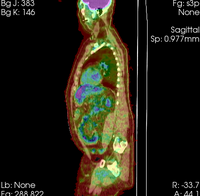

Slicer Registration Use Case Exampe #8: Intra-subject whole-body PET-CT

this is the fixed reference image. All images are aligned into this space lleft this is the moving image. The transform is calculated by matching this to the reference image LEGEND

lleft whole body CT + PET baseline lleft whole body CT + PET follow-up

CT: 512 x 512 x 267

0.97 x 0.97 x 3.27 mm

PET: 128 x 128 x 267

4.7 x 4.7 x 3.3 mm